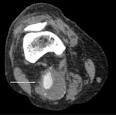

Pseudoaneurysm

Popliteal Aneurysm

- history of aortic aneurysm

- claudication

- rest pain

- acute limb ischemia

Physical Exam

- palpation of popliteal fossa

- pedal pulse exam

- ABI